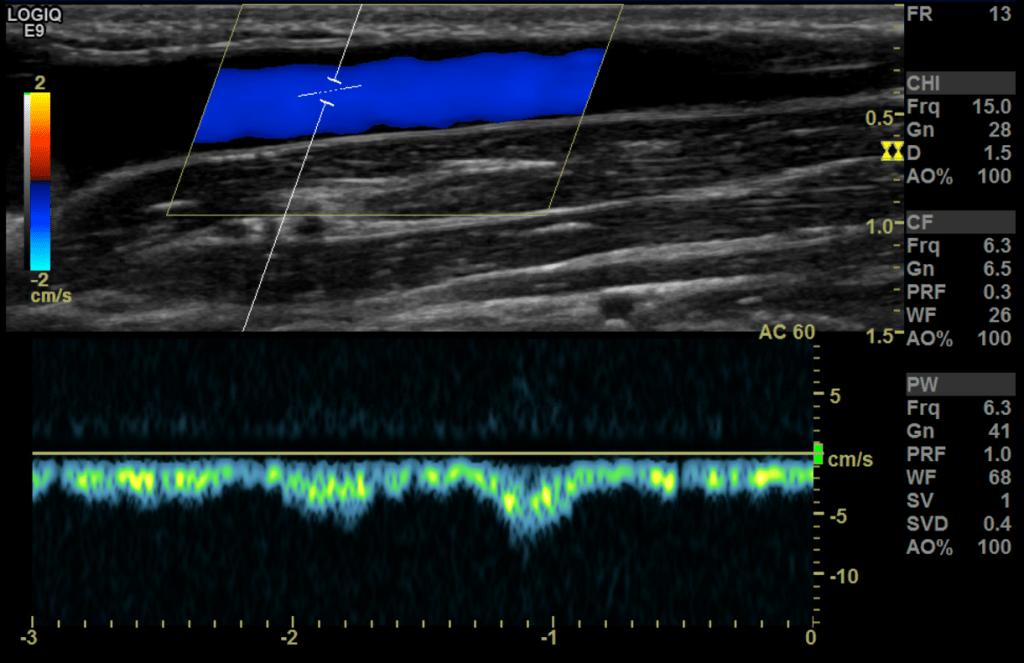

Upper extremity Vein

The flow in a normal vein is monophasic and has very little phasicity with normal breathing and cardiac patterns with increased reversal of flow after distal augmentation

Next we assess the outflow stream (venous side) starting with the subclavian/cephalic vein confluence at the shoulder level followed by the bicep and forearm segments of the outflow stream evaluating for abnormalities such as thrombus, stenosis, occlusions, PSA/aneurysms, etc.

Sample the venous anastomosis side a few times the highest sampled here is PSV/EDV as 500/170 cm/s.